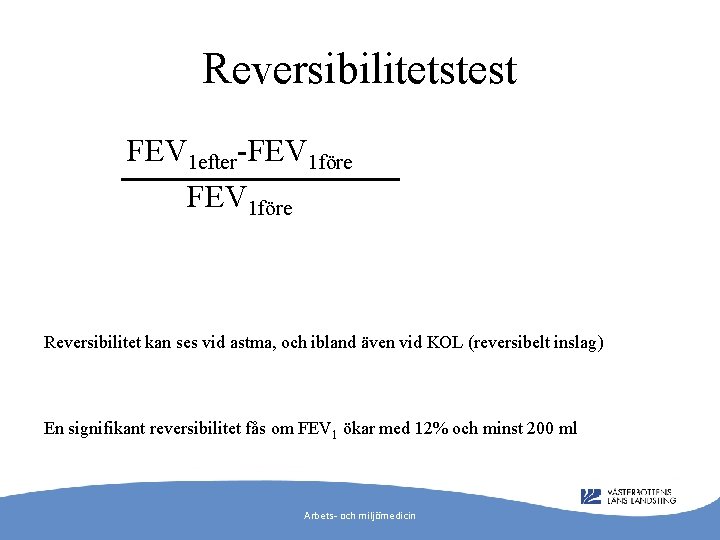

Reversibilitetstest FEV 1 efter-FEV 1 före Reversibilitet kan ses vid astma, och ibland även vid KOL (reversibelt inslag) En signifikant reversibilitet fås om FEV 1 ökar med 12% och minst 200 ml Arbets- och miljömedicin